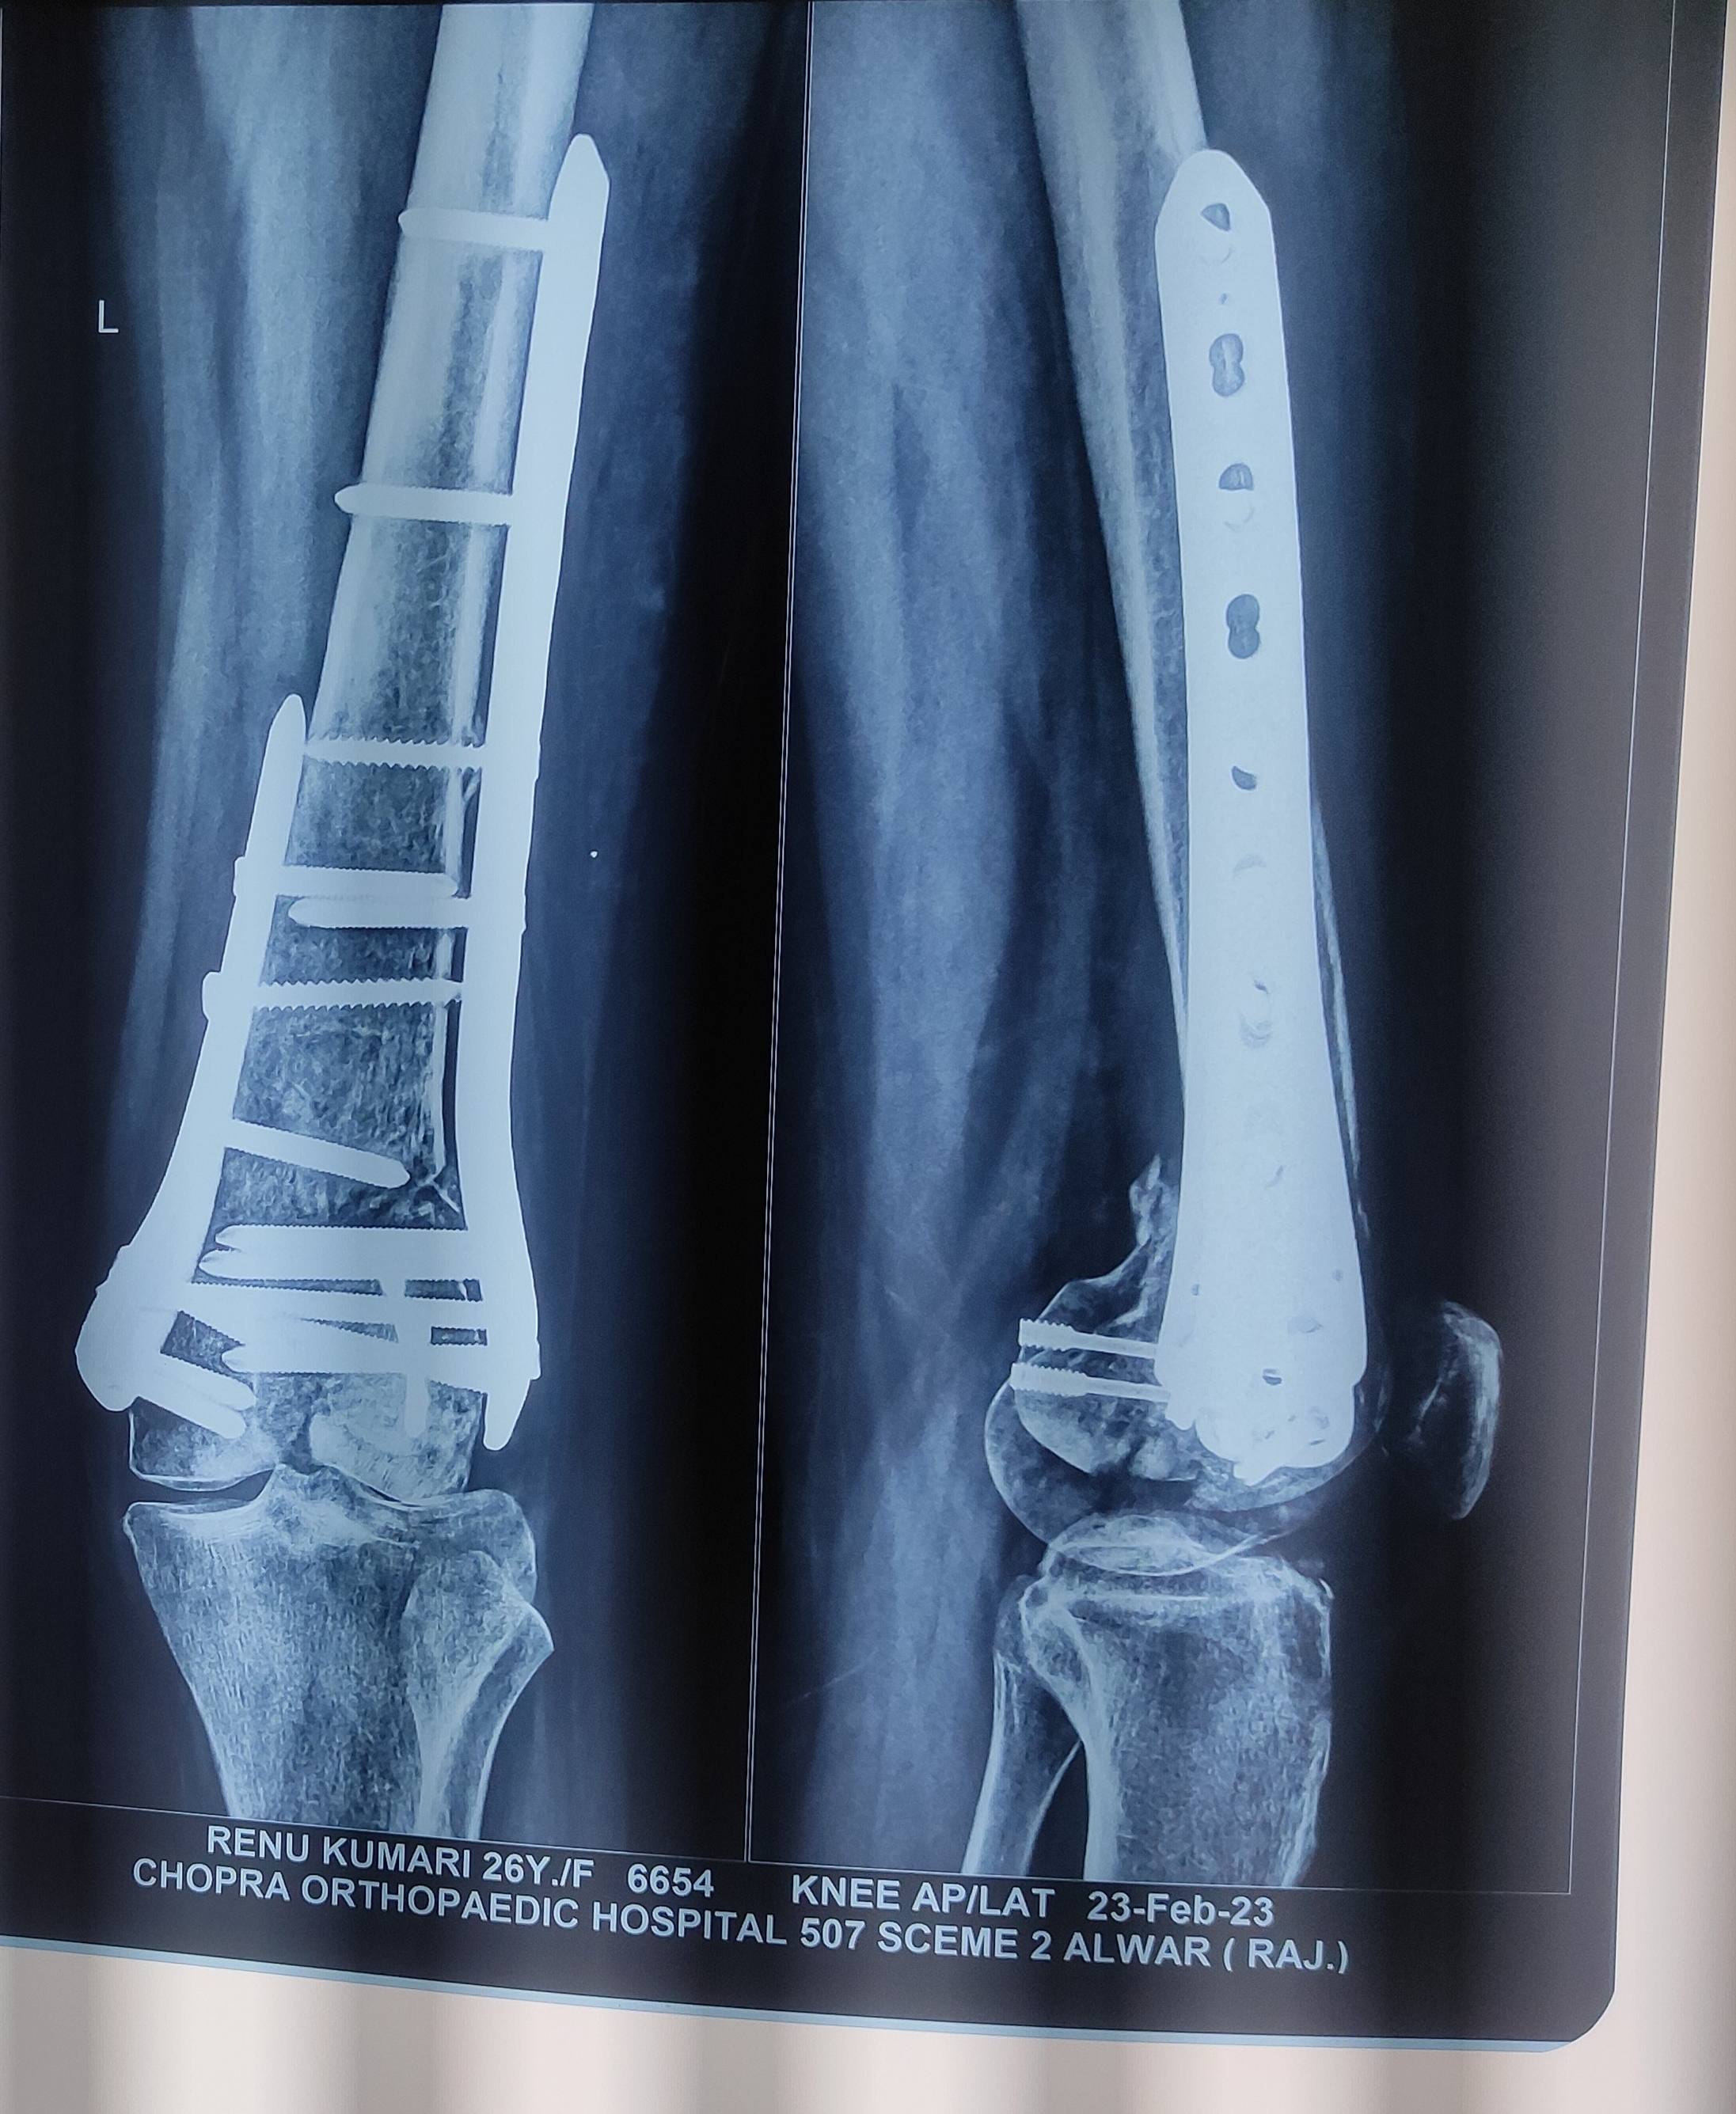

Bone fracture

Sir mera distal femur fracture hua surgery ko 4 month hogye h knee 40 to 45 tk hi bend hota h sir please reply m orthoscopy surgery kb tk krwa skti hu. Knee bhut stiff h.